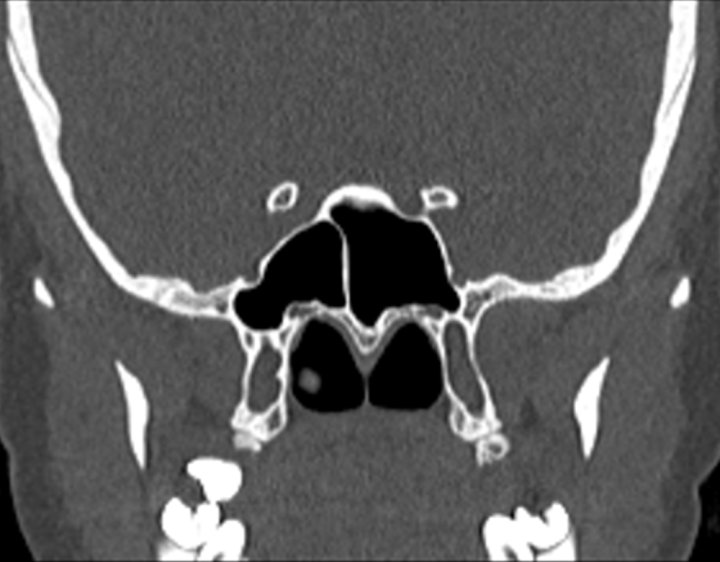

Click any image for labels.